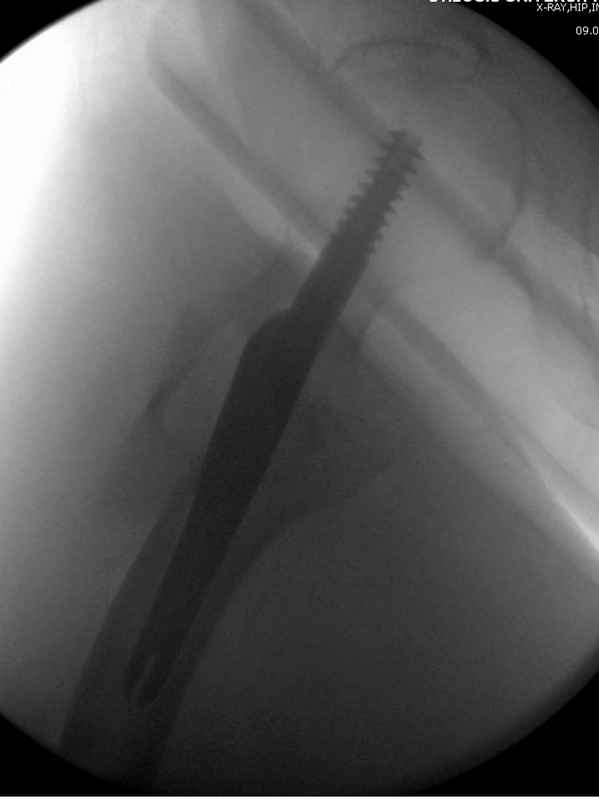

Здесь 83 года, травма в результате падения

Djoldas Kuldjanov, M.D.

Department of Orthopedic Surgery

St. Louis University

судя по картинкам с ЭОПа явно использовались приемы непрямой репозиции под его контролем, а так же интраоперационный ЭОП-контроль положения винтов, без такого контроля операция может ухудшить ситуацию (опять же учтите сроки) т.к. результат буде зависеть в большей степени от искусства хирурга, а не от технологии